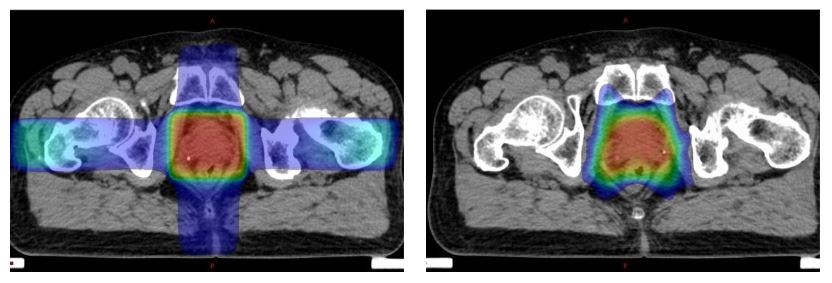

이 화상은 전립선암에 대해 통상 조사(왼쪽)와 IMRT(오른쪽)로 비교한 것입니다.

IMRT 쪽은 화면 아래쪽이 움푹 들어가 있는 것을 알 수 있을 거라고 생각합니다. 고선량의 부분(색이 붉은 부분)이 우수한 직장을 피하고 있습니다.

IMRT가 널리 쓰이게 되면서 전립선암은 보통 조사 때보다 더 많은 방사선을 조사할수 있게 되어 치료 성적이 향상된 암 중 하나입니다.